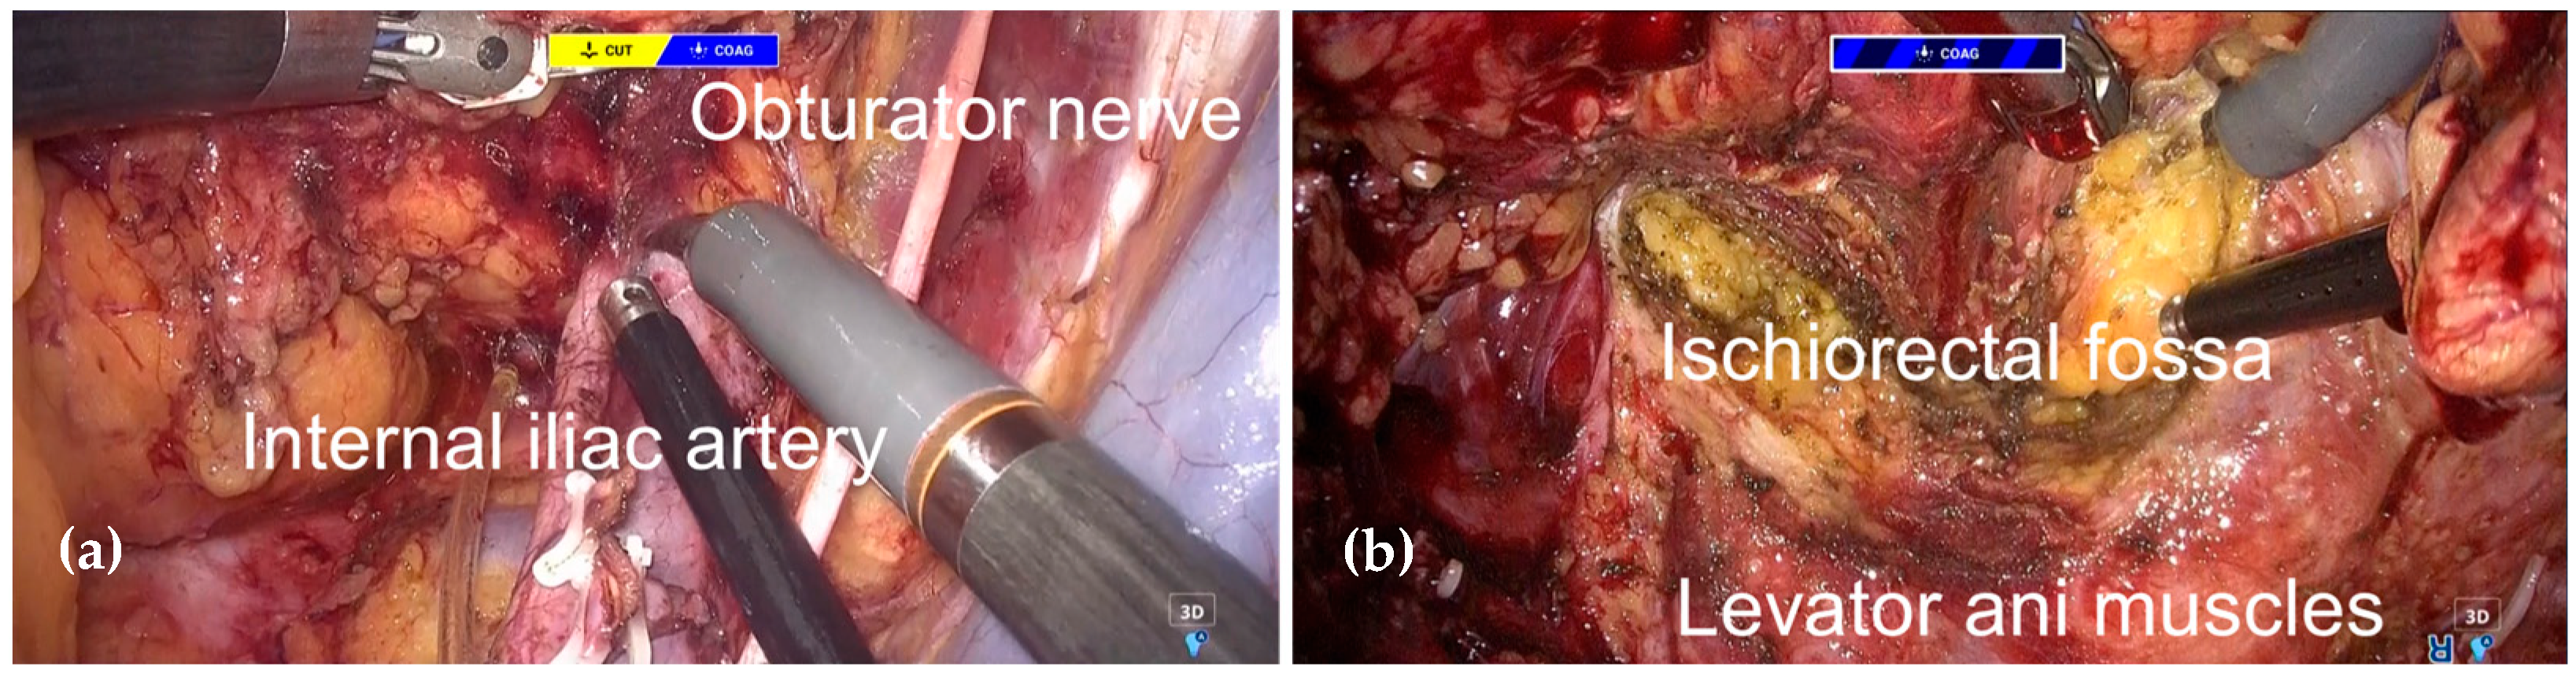

2.3. Surgical Procedure